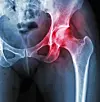

Suomessa yli 45-vuotiaista noin kuusi prosenttia sairastaa lonkkanivelrikkoa. Brittitutkijat ovat havainneet lonkkaniveleen pistettävän kortikosteroidipistoksen helpottavan potilaiden kipuja ja parantavan toimintakykyä. Pistoksen vaikutus on tehokkain 2-4 kuukauden sisällä pistoksesta. Toistaiseksi kortikosteroidipistoksia käytetään yleisemmin polven nivelrikon hoidossa.